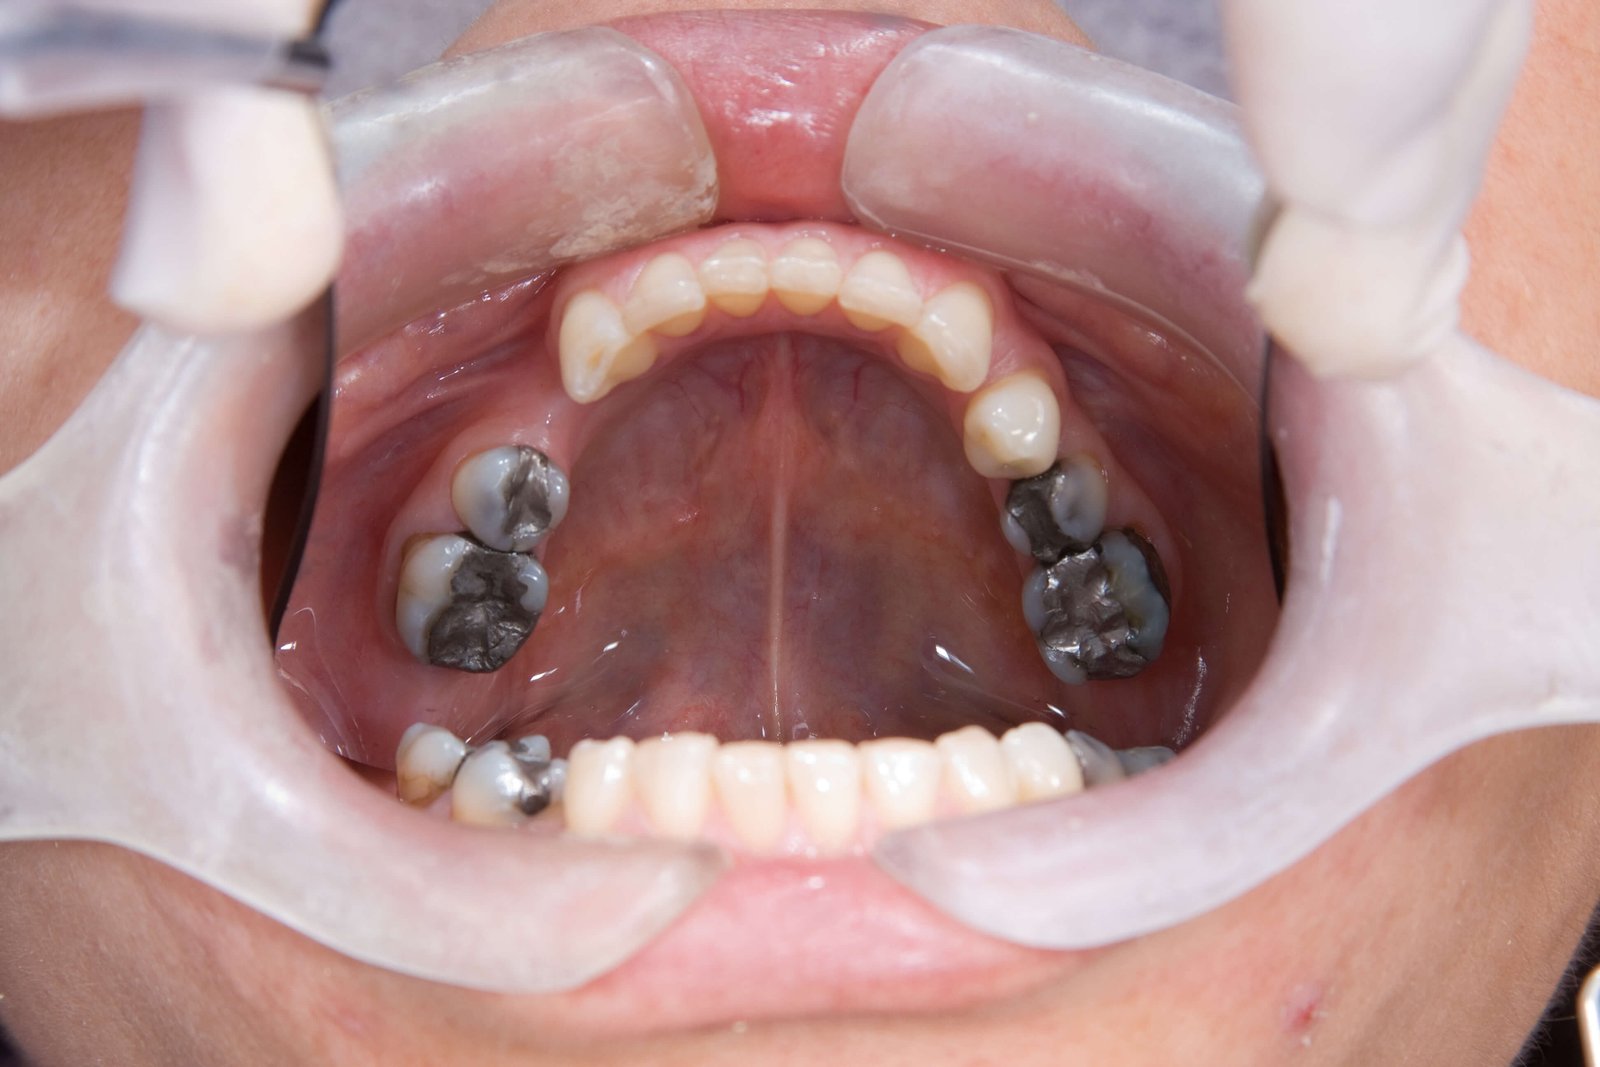

• Amalgama: mezcla metálica de mercurio, plata, estaño y cobre. Su color gris metálico rompe con la estética natural de la sonrisa.

• Apariencia metálica poco estética.

• Genera manchas en el diente y tatuajes en las encías.

• No se adhiere al diente, lo que favorece microfiltraciones bacterianas y sensibilidad.

• Puede volver el diente más frágil y propenso a fracturas catastróficas.